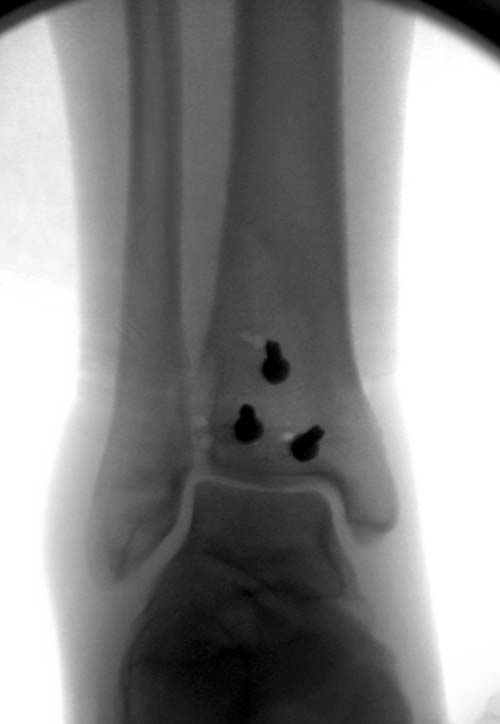

Первый случай, где перелом в результате падения с  небольшой высоты, где

мортиз рентген снимок показал отстутствие укорочения наружной

лодыжки и КТ срезы подсказали направления атаки. После такой фиксации

нет надобности в гипсовой повязке, брейс и через две недели движения в

суставе без нагрузки.